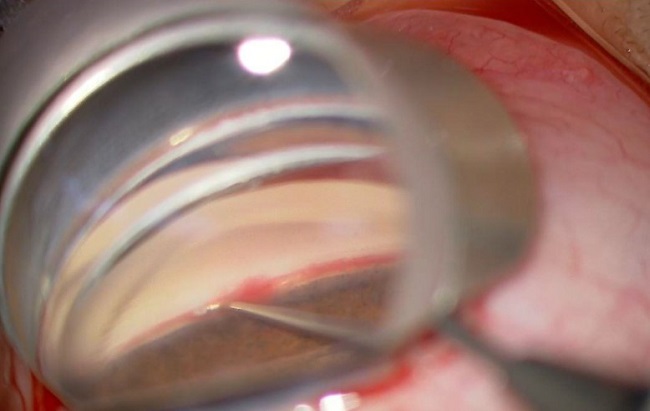

Gambar 1. Prosedur Trabekulotomi untuk Glaukoma.